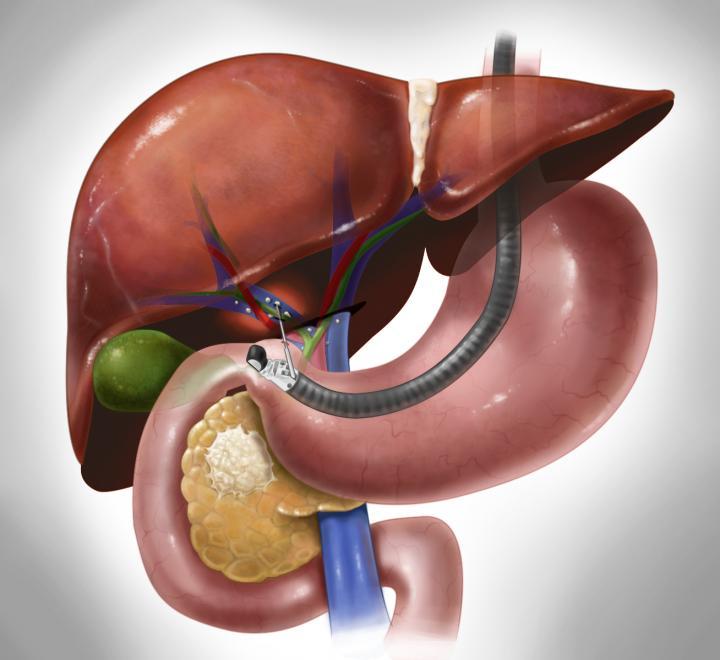

منظار القنوات المرارية هو أحد أهم الوسائل الحديثة لتشخيص وعلاج انسدادات القنوات المرارية ومشاكل الجهاز الصفراوي، وهو إجراء يتم باستخدام منظار خاص عبر الفم للوصول إلى القنوات المرارية والصفراوية.

منظار القنوات المرارية هو إجراء يستخدم فيه الطبيب منظارًا مرنًا مزودًا بكاميرا ليدخل من خلال الفم ويمر بالمعدة حتى يصل إلى الجزء العلوي من الأمعاء الدقيقة (الاثني عشر)، حيث تفتح القنوات المرارية. ومن خلال هذا المنظار، يمكن للطبيب رؤية القنوات الصفراوية واكتشاف الحصوات أو الضيق أو أي مشكلات أخرى.